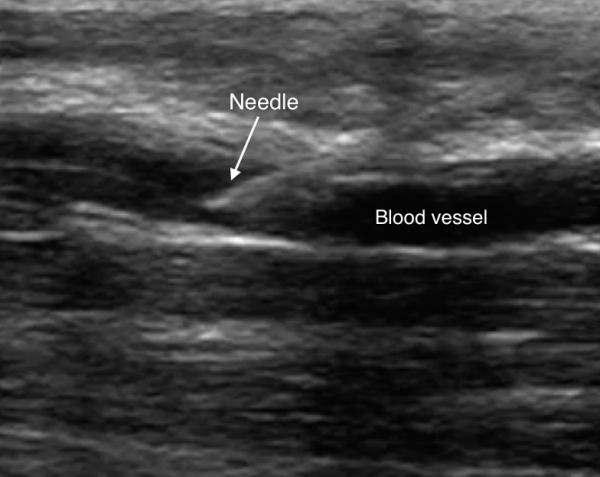

4. Identify the hyperechoic needle tip on the right side of the screen.

5. Advance the needle tip until you visualize it piercing the wall of the vessel on the screen— you will see a corresponding flash of blood in the catheter once the needle has pierced the vessel.

Image 6. Hyperechoic needle tip localized in a blood vessel in long axis. Image Courtesy of Sierra Beck, MD and Bradley Wallace, MD.